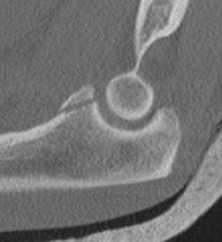

O'Driscoll classification anteromedial coronoid facet fractures

| Type I | Type II | Type III |

|---|---|---|

| Transverse fractures | Anteromedial facet fractures | Basilar fractures |

| Lasso suture fixation |

Lasso suture fixation - small Medial buttress plate / screws - large |

Dorsal +/- medial plate |

|

|

|

Anteromedial coronoid facet fragment

- associated with varus posteromedial rotational force

- associated with tear of lateral ulna collateral ligament (LUCL)